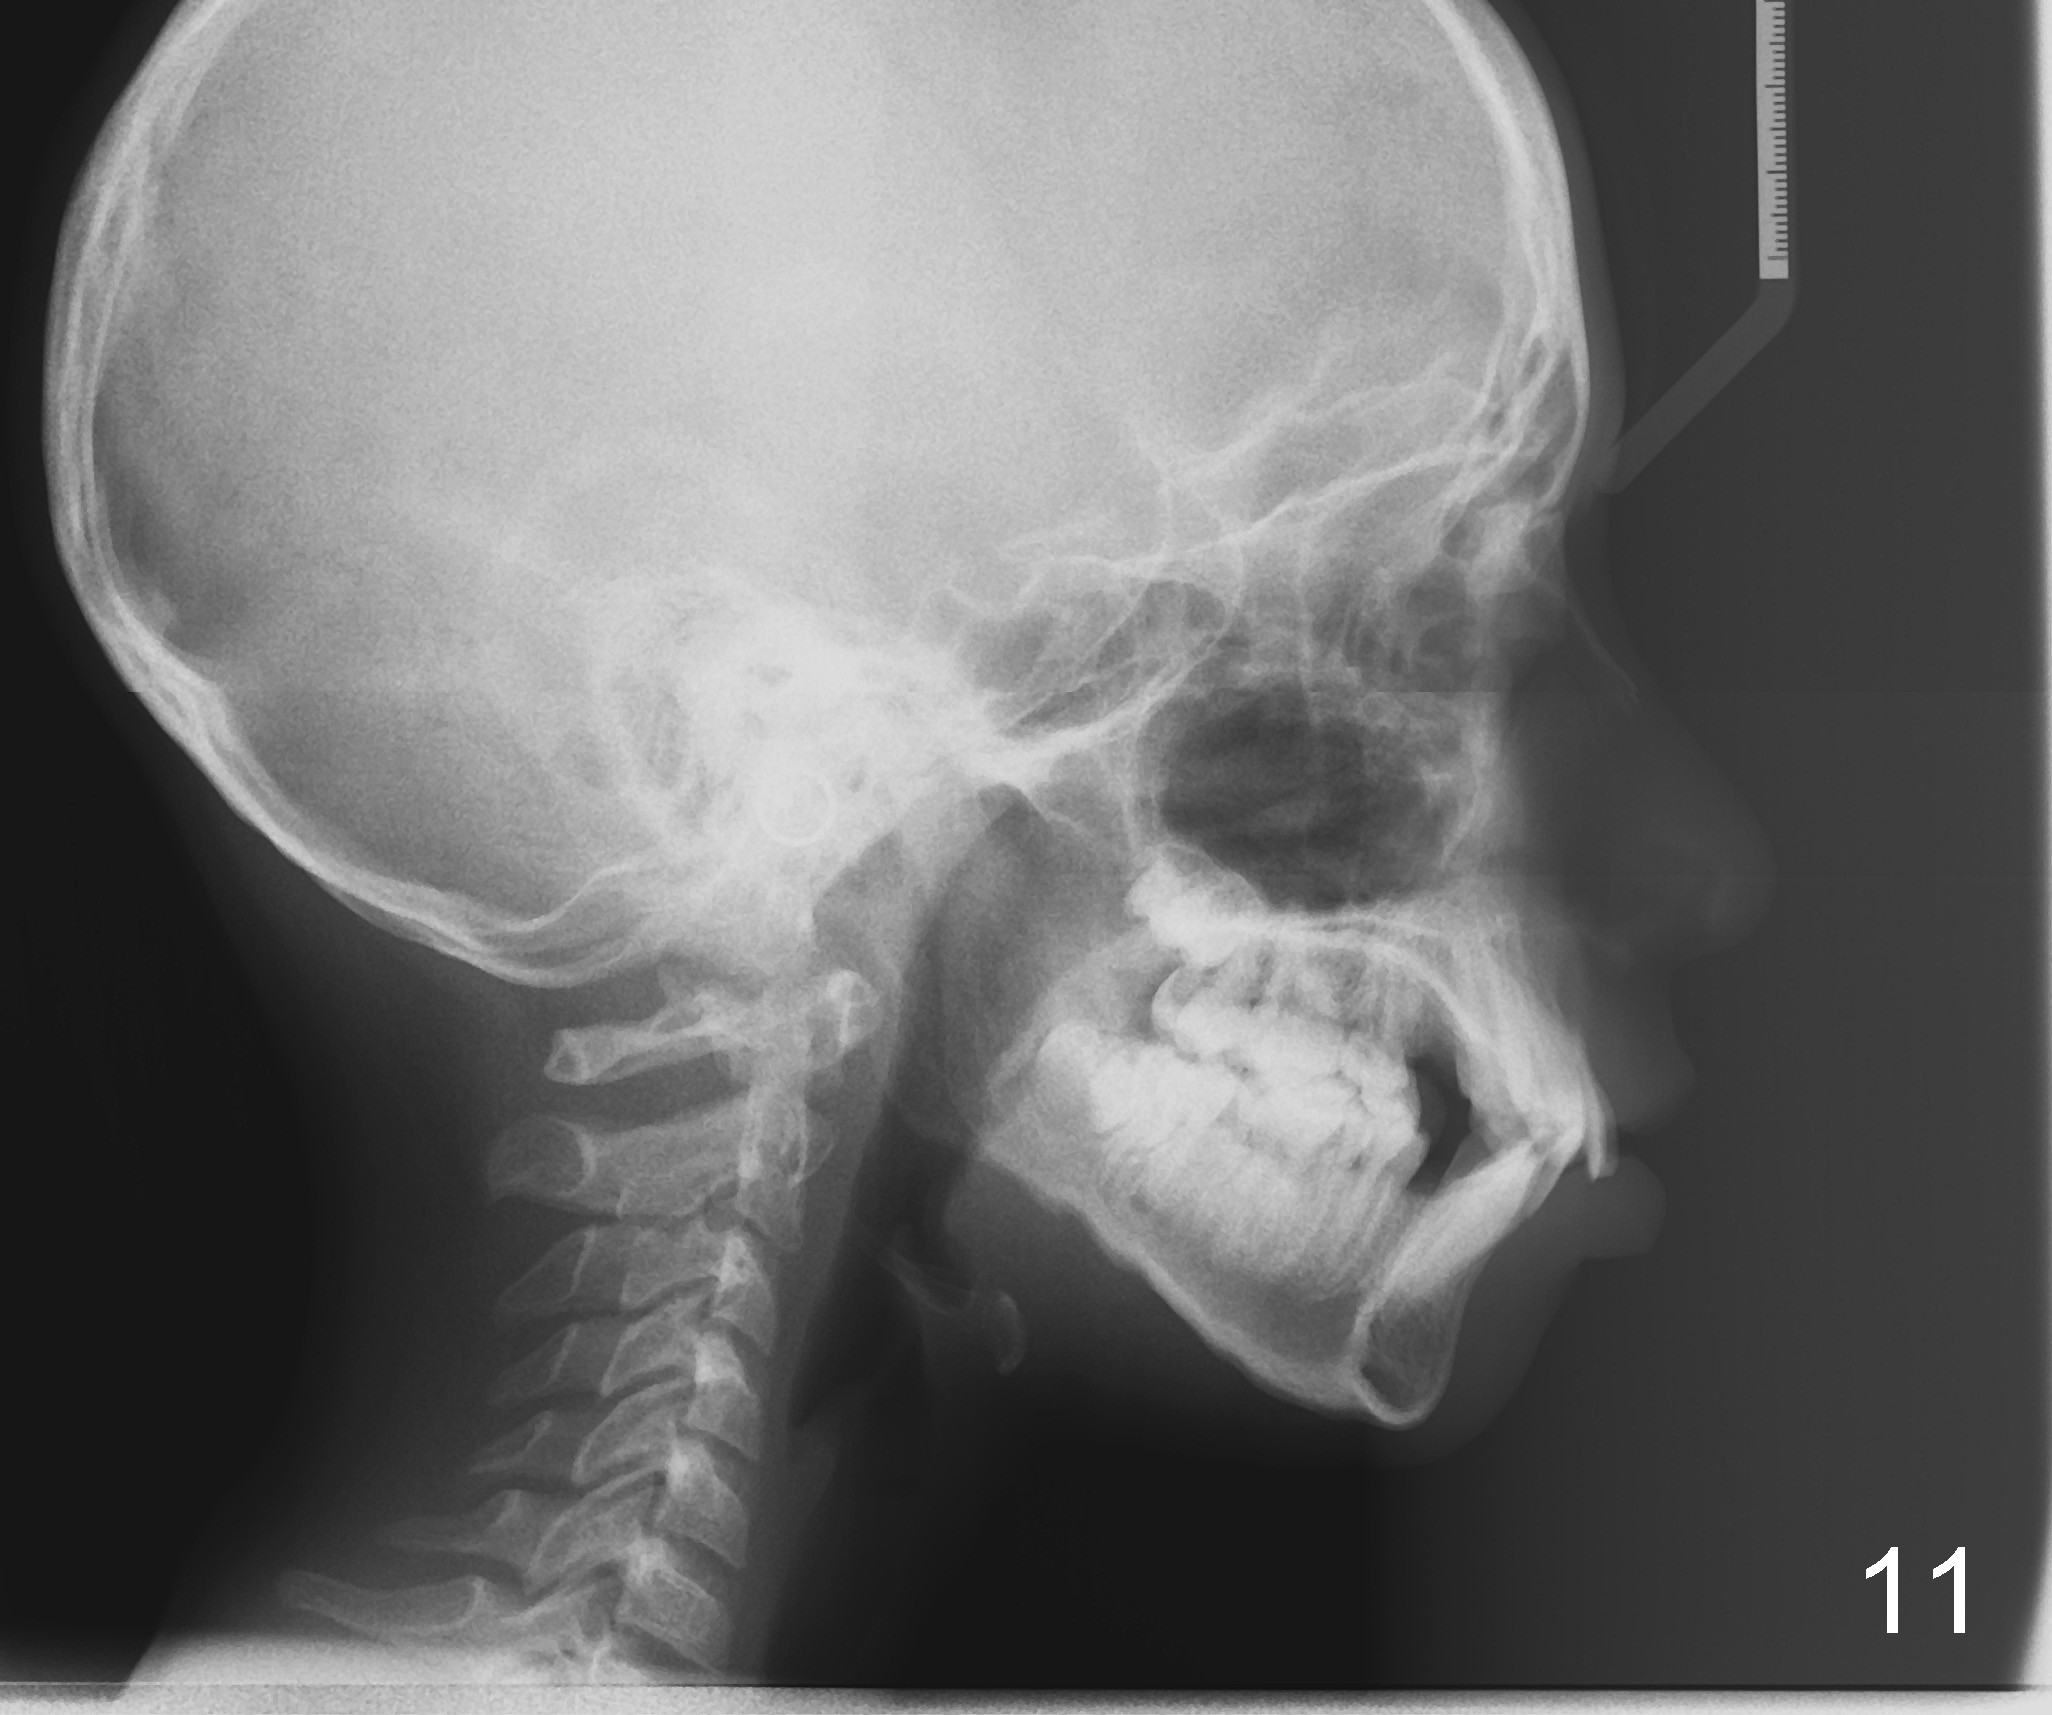

Photos were taken on May 29, 2012 (Fig.1-8), ceph and pan May 24, 2012 (Fig.9,10), post-extraction ceph July 30, 2012 (Fig.11).